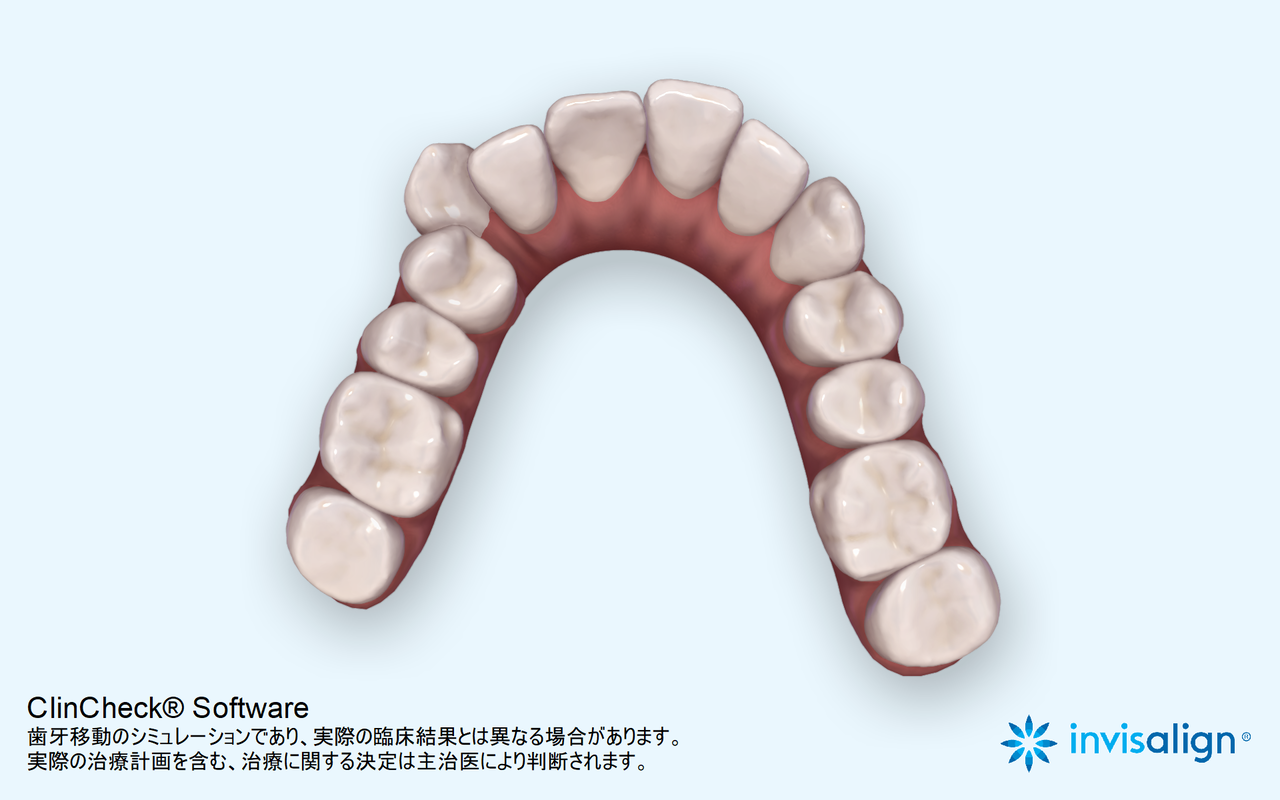

マウスピース矯正を開始して

2025年1月5日 わずか9か月後の状態。

上の歯。引っ込んだ歯が歯並びの中に納まっている。

下の歯。こちらも歯並びの中に納まっている。

横からは、やや出っ歯だったのが、出っ歯感はなくなった。

患者さんは平成23年生まれの13歳とあごの成長が残っている世代だった為、あごの成長をコントロールすることもできわずか10か月で終了することができた。